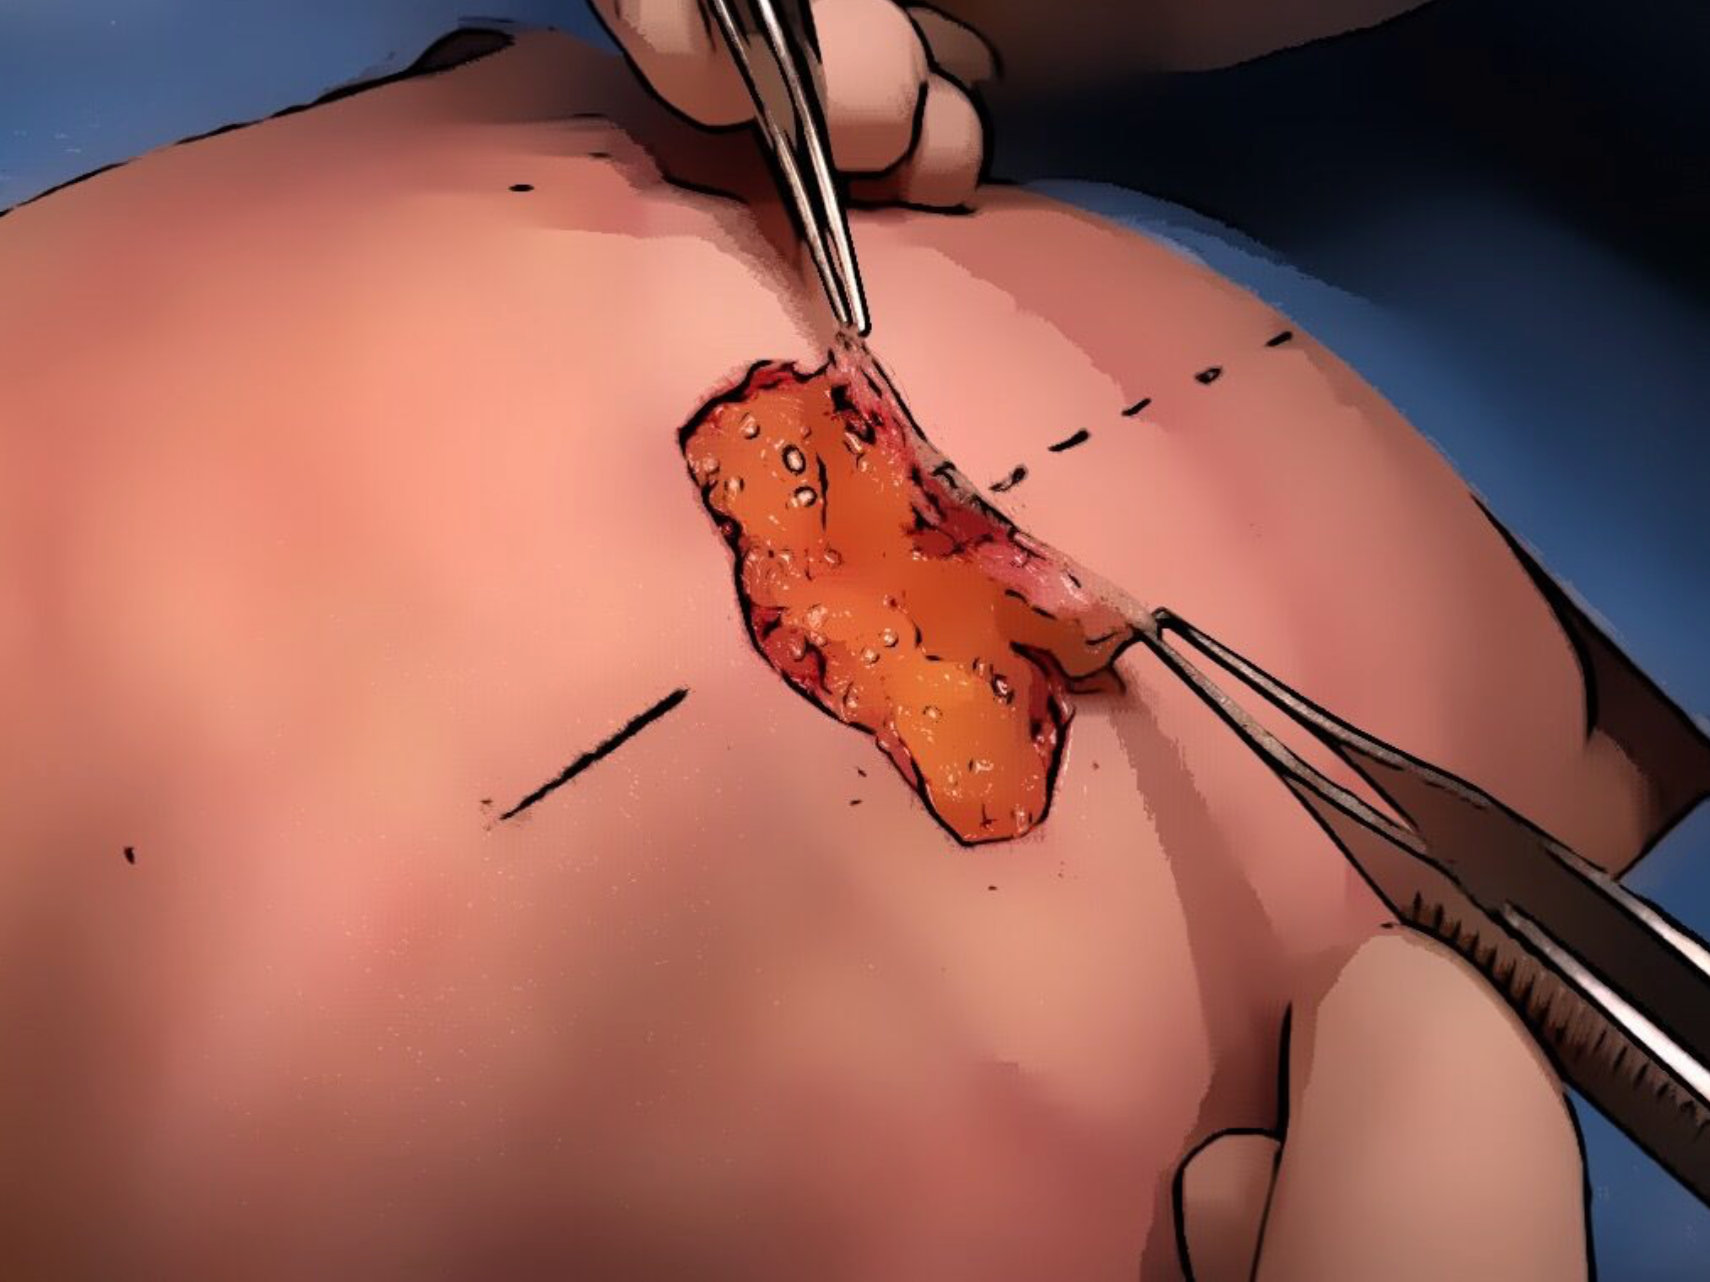

Verwijderen DIEP flap

Enkel huid- en vetweefsel worden verwijderd ter hoogte van de buikregio (onder de navel). De buikspieren blijven intact.

Opzoeken bloedvat

Het bloedvat dewelke de DIEP flap voorziet van bloeddoorstroming wordt opgezocht. Dit bloedvat wordt een perforant genoemd en werd gelokaliseerd door een CT scan uit te voeren voor de ingreep.